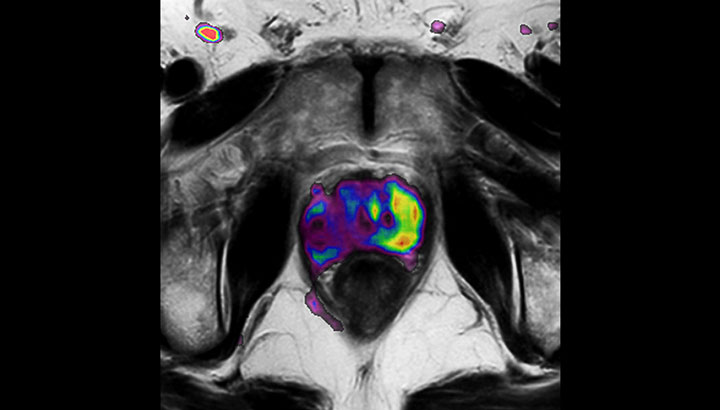

With its exceptional soft-tissue visualization capabilities and wide range of image contrasts, MRI has become a powerful tool to help more precisely define tumor boundaries. This is particularly important as it has been established that there is a high degree of uncertainty in target volume delineation, and it is even reported to represent the largest uncertainty in the entire radiotherapy process for most tumor sites**. Better visualization of the target area and nearby organs-at-risk is a key factor in enhancing target volume delineation. MRI’s expanding role also can be attributed to its functional imaging capabilities, which can inform both target characterization and treatment response.

The ability to tune contrasts can provide even more valuable information about tumor characteristics and tumor extent to facilitate enhanced delineation, and also provides possibilities for dose boosting strategies.

In addition to anatomical imaging, MRI offers the ability to obtain functional information that is beneficial for tumor detection and delineation, and for response monitoring.

Diffusion-weighted imaging (DWI) for example depicts areas of high signal intensity in soft tissues that are indicative of the restricted water mobility (i.e., diffusion) of a tumor and can also be used to identify lymph nodes. Changes in the tissue’s or lesion’s apparent diffusion coefficient (ADC) can provide insights that help predict the tumor’s response to radiotherapy.